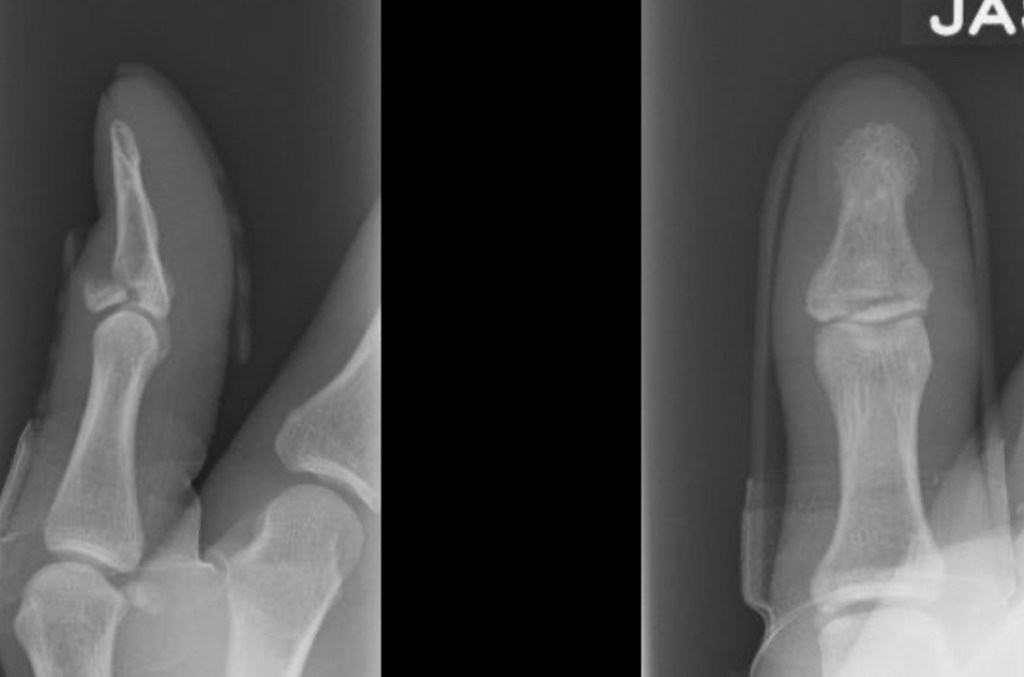

A mallet injury refers to a tear in the tendon that straightens the end joint of your finger. This can be simply a tear is the tendon (soft tissue mallet) or a piece of bone can come off with the tear (bony mallet).

The diagnosis is made clinically on the basis of the mechanism of injury, and the presence of tenderness over the end finger joint, with an inability to fully straighten the finger (this is known as an extensor lag). An X-ray will often be performed to look for any fractures.

Mallet fingers are generally STABLE injuries – there is a very small risk of dislocation of the joint associated with a simple mallet injury. The presence of a fracture on xray can indicate a more severe injury, and if the bony fragment is large, the injury should be considered potentially UNSTABLE. This distinction is important because an unstable injury may need an operation to ensure that the end finger joint does not dislocate.